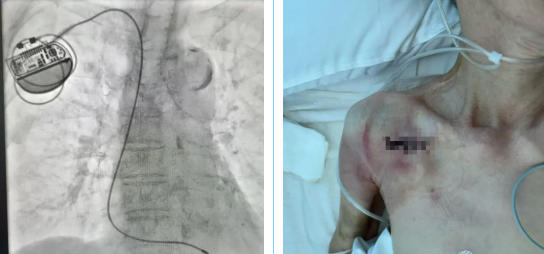

何丽团队全面评估,并与家属充分沟通后,最终“量身定制”最佳手术方案——单腔起搏器植入术。近日,手术团队通过一个微小切口,将一枚小巧的单腔起搏器成功植入陈奶奶胸前。术后,老人生命体征平稳,未再出现黑矇或晕厥,转入骨科接受后续治疗。

何丽指出,单腔起搏器虽然结构相对简单,却能够胜任“心脏安全卫士”的核心职责——当心脏停跳超过预设时间时,立即发放电脉冲,确保心脏不“罢工”,具有手术时间短、创伤小、囊袋相关并发症风险低等优势。